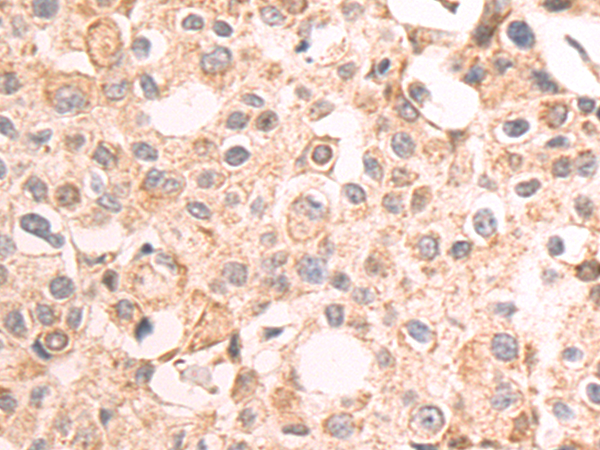

分类: 科研抗体货号: P07969别名:应用: IHC反应种属: Human, Mouse